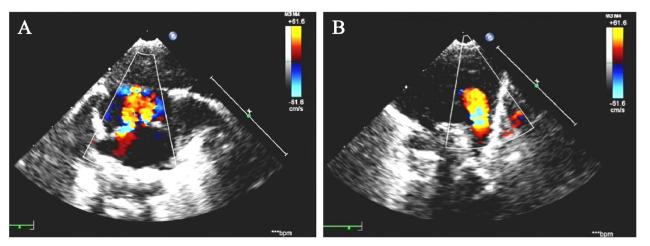

患儿男,出生7 d,系孕36+3周自然受孕早产儿。母亲G1P1,产前未在本院规律产检,孕早期唐氏综合征筛查未见异常,停经14+周外院彩色多普勒超声(彩超)提示胎儿大小约12+4周,颈项透明层厚度(NT)值为2.5 mm。孕中期外院三维彩超未见明显异常。母亲36+3周外院产检发现胎心持续反应差,无下腹部疼痛,阴道无流血、流液,自觉胎动如常,予胎心监护、静脉输液治疗未见改善,遂至我院急诊就诊,拟诊胎儿宫内窘迫,行剖宫产,娩出一男性新生儿。患儿出生时体重2 850 g,身长48 cm,出生后查体反应可,前囟平软,哭声不扬,口唇微绀,双手多指畸形(六指)。辅助检查:血尿粪常规,甲状腺功能,电解质,肝功能等均正常。性激素6项:睾酮3.03 nmol/L,卵泡刺激素< 0.30 IU/L,催乳素1 431.6 mIU/L,孕酮6.89 nmol/L,黄体生成素< 0.07 IU/L,雌二醇88.02 pmol/L。彩超提示:右侧阴囊内睾丸缺如,右侧腹股沟隐睾,左侧睾丸及附睾未见明显异常;肺动脉高压(重度),动脉导管未闭,房间隔缺损(多孔,继发孔型),室间隔小缺损(肌部),三尖瓣反流(轻度),右心房右心室增大,左心室收缩功能正常,见图1。患儿父母非近亲结婚,否认家族遗传病史,无既往病史。

图1 一例PMS患儿的彩超结果

注:A为房间隔缺损;B为动脉导管未闭。